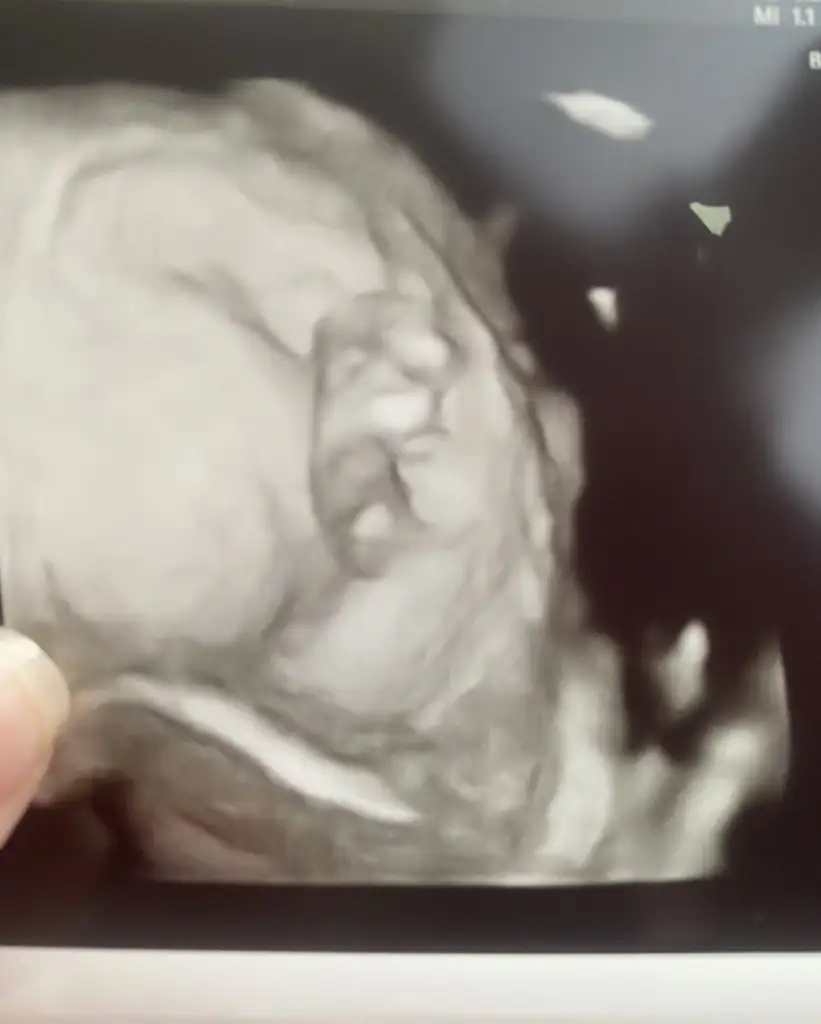

Aiyy cinsiyetle alakalı bir şey söylemedi ama ultrason cihazı iyi gibi muhtemelen. Baksanıza atayım 9+5 için iyi görüntüler benceAllah minik kızını sağlıkla kucağına almayı nasip etsin canım beniminşallah zamanla daha iyi olacağız ben de teşekkür ederim duaların için

Ay maşallahAiyy cinsiyetle alakalı bir şey söylemedi ama ultrason cihazı iyi gibi muhtemelen. Baksanıza atayım 9+5 için iyi görüntüler bencebu arada şu gördüğüm burun değildir demi bi de bebiş neden bu kadar sinirli yaaa

Çis yapmaya başlamış mı acaba sanki ordan yukarıya doğru çıkan birşey var çiş gibiAiyy cinsiyetle alakalı bir şey söylemedi ama ultrason cihazı iyi gibi muhtemelen. Baksanıza atayım 9+5 için iyi görüntüler bencebu arada şu gördüğüm burun değildir demi bi de bebiş neden bu kadar sinirli yaaa

Ay maşallaherkek ben de ilk yuzunun ustundekini burun sandım ama sağ kolunu kaldırmış da olabilir...

Ayy bende erkek gibi gördüm valla ins hakkında hayırlısı olsun sağlıkla gelsinAiyy cinsiyetle alakalı bir şey söylemedi ama ultrason cihazı iyi gibi muhtemelen. Baksanıza atayım 9+5 için iyi görüntüler bencebu arada şu gördüğüm burun değildir demi bi de bebiş neden bu kadar sinirli yaaa

Bu arada bana da erkek gibi geldiAiyy cinsiyetle alakalı bir şey söylemedi ama ultrason cihazı iyi gibi muhtemelen. Baksanıza atayım 9+5 için iyi görüntüler bencebu arada şu gördüğüm burun değildir demi bi de bebiş neden bu kadar sinirli yaaa

Genital organlar 10.haftadan itibaren oluşmaya başlıyor bu nedenle erken henüz canımAiyy cinsiyetle alakalı bir şey söylemedi ama ultrason cihazı iyi gibi muhtemelen. Baksanıza atayım 9+5 için iyi görüntüler bencebu arada şu gördüğüm burun değildir demi bi de bebiş neden bu kadar sinirli yaaa